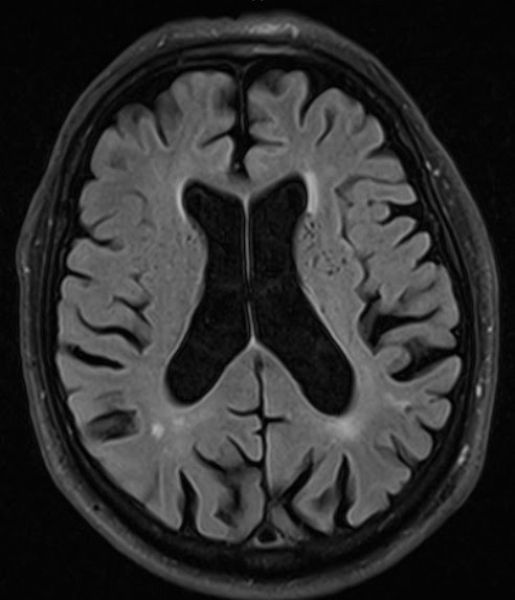

Хроническая ишемия головного мозга и лейкоареоз: симптомы и лечение